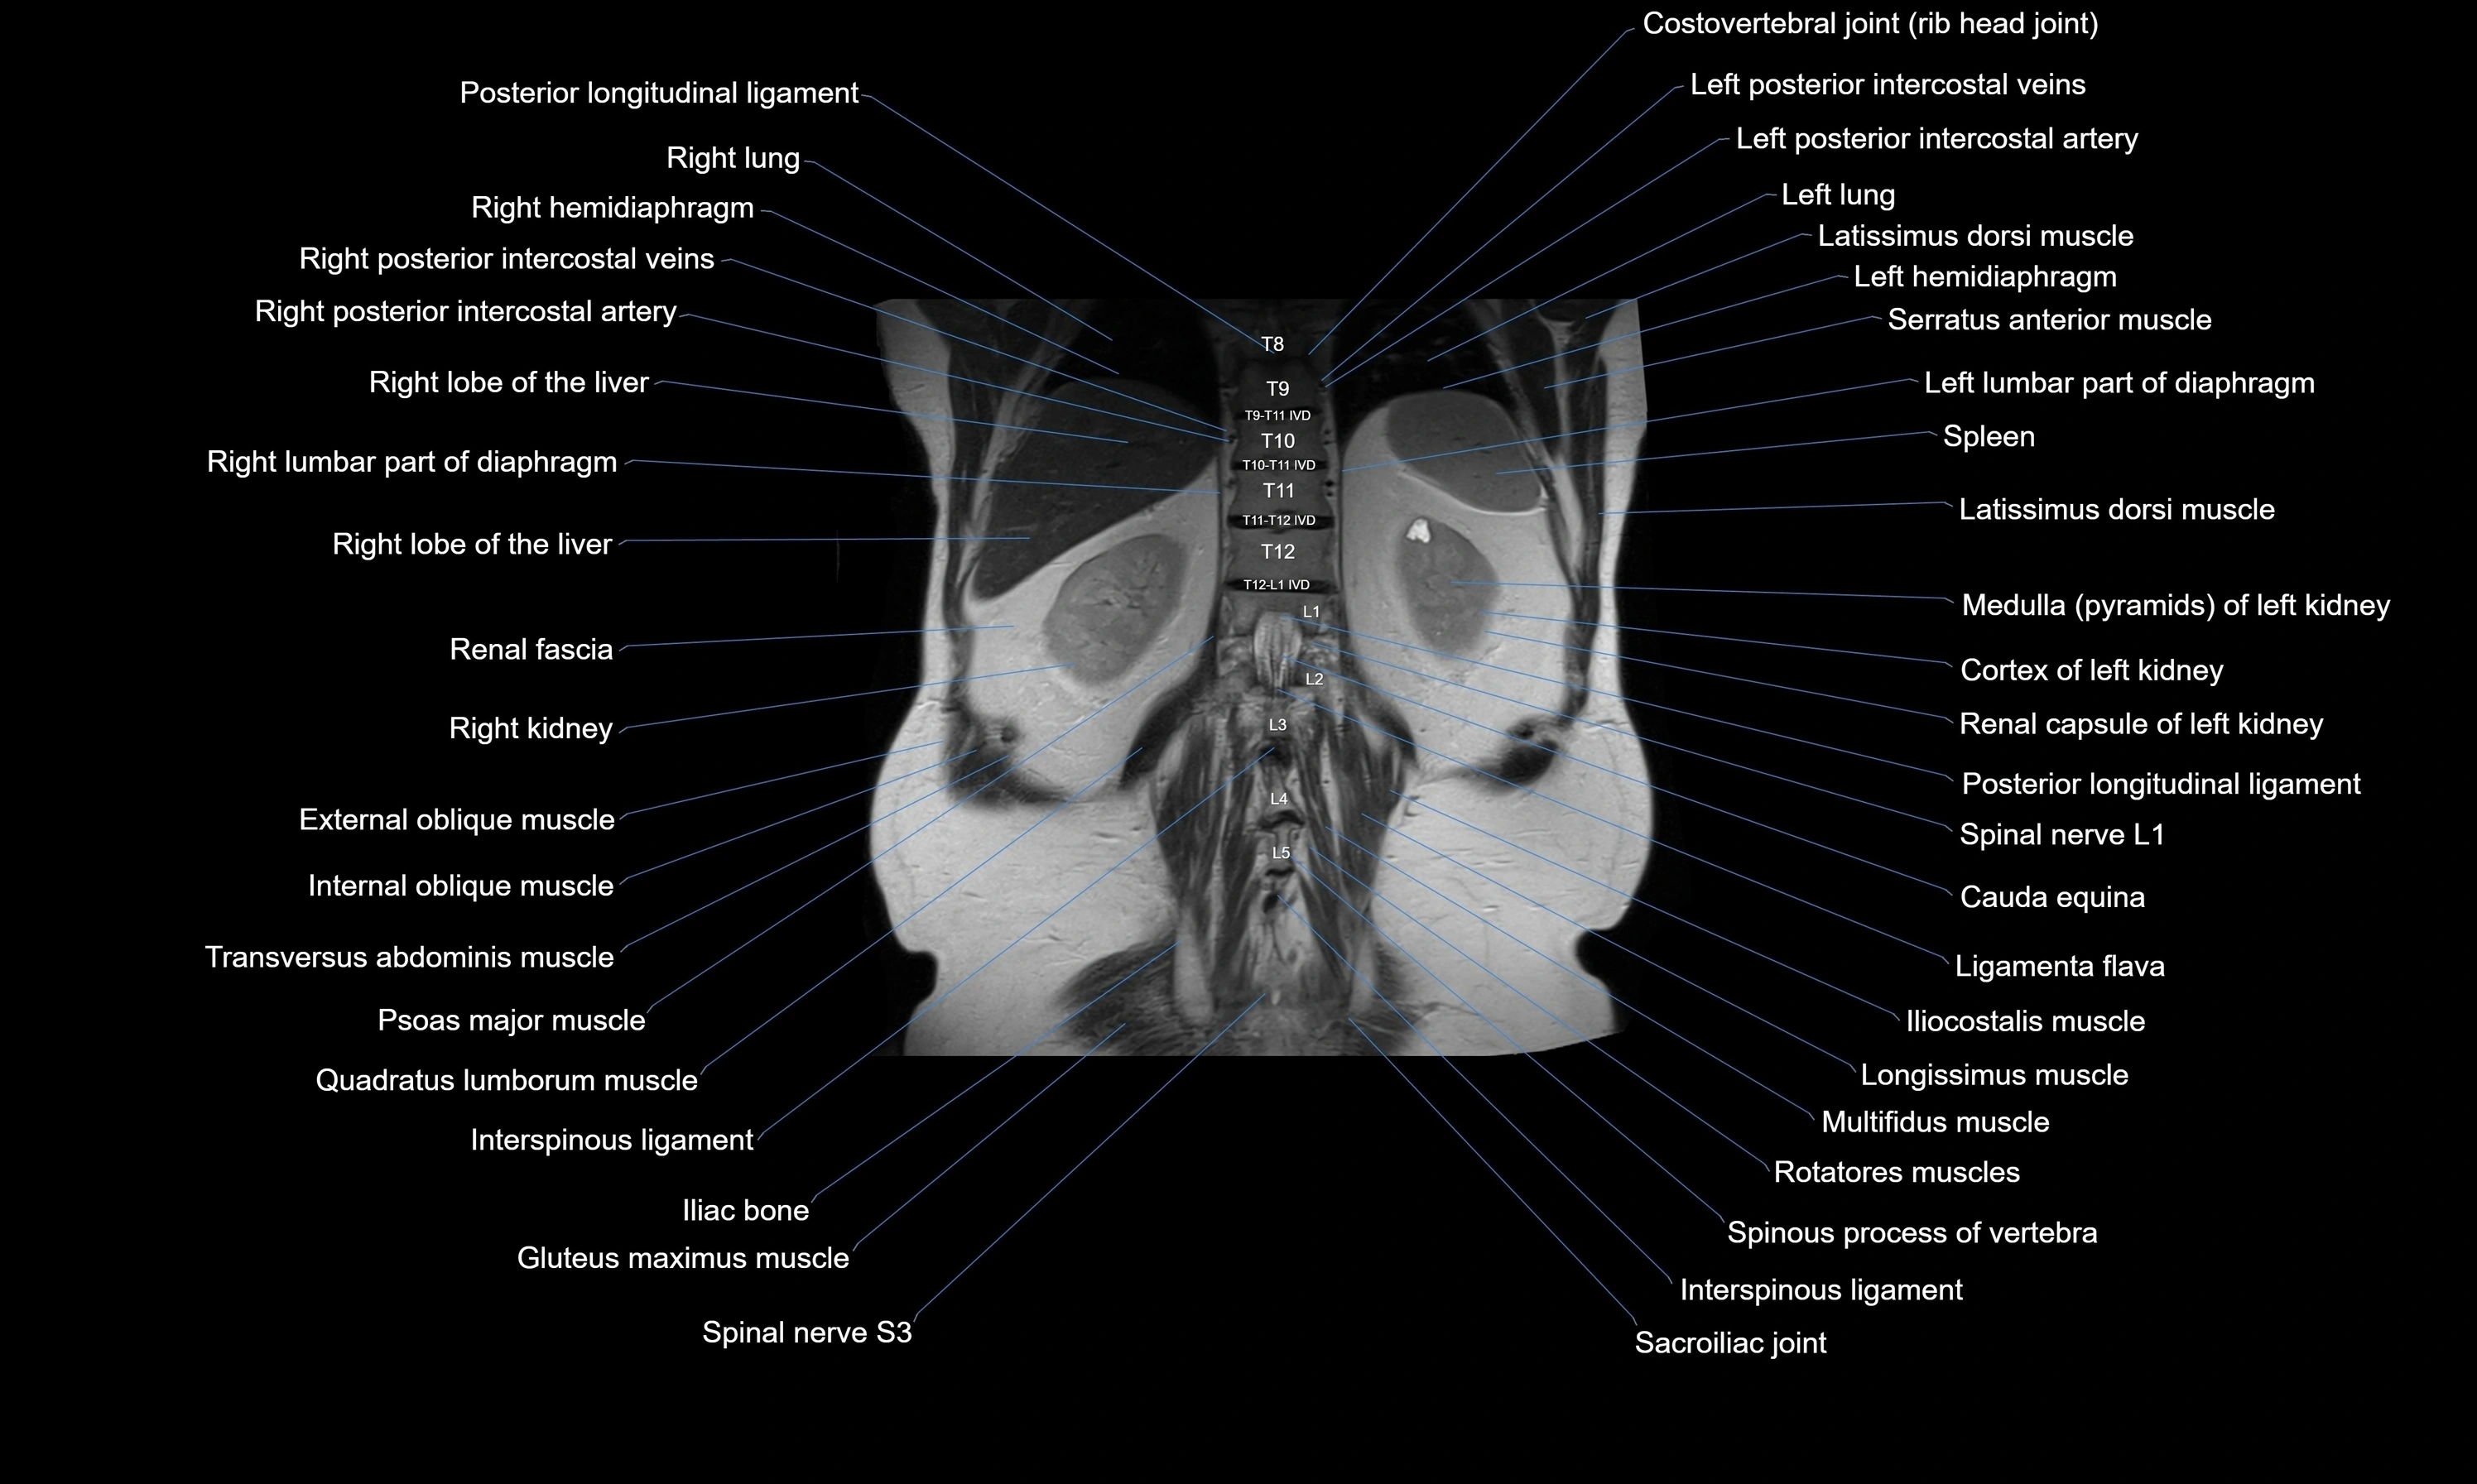

MRI images